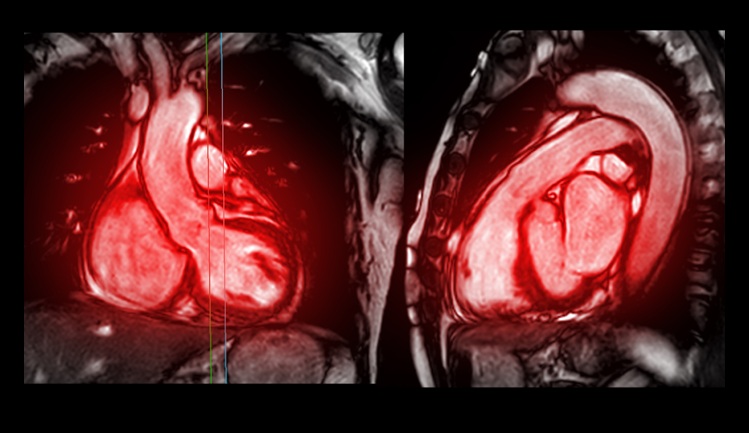

- New MRI Technique Reveals Hidden Heart Issues

- MRI Scans Can Identify Cardiovascular Disease Ten Years in Advance